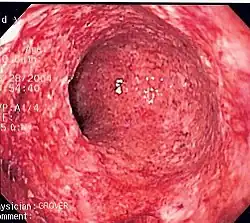

- Ulcerative inflammation: Inflammation occurring near an epithelium can result in the necrotic loss of tissue from the surface, exposing lower layers. The subsequent excavation in the epithelium is known as an ulcer.

Disorders

Inflammatory abnormalities are a large group of disorders that underlie a vast variety of human diseases. The immune system is often involved with inflammatory disorders, as demonstrated in both allergic reactions and some myopathies, with many immune system disorders resulting in abnormal inflammation. Non-immune diseases with causal origins in inflammatory processes include cancer, atherosclerosis, and ischemic heart disease.[9]